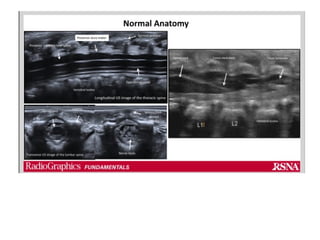

• US can identify anatomical landmarks and the depth of the

epidural space.

• It also allows for needle visualisation and epidural catheter

advancement within the epidural space in neonates and infants.

• The ability of US to produce an image is impeded by bone, and

therefore, with increasing age and increased ossification, less of the

spinal column contents can be observed.

• Because of this fact, imaging of the spine in neonates can be done

with the transducer in the midline longitudinal position; however, in

infants and older age groups, a paramedian longitudinal approach is

used to obtain a view through the interlaminar space.

• Paramedian longitudinal and the intervertebral axial planes

provide the best view of the spinal anatomy but the ultrasound

window size decreases with increasing age due to ossification.